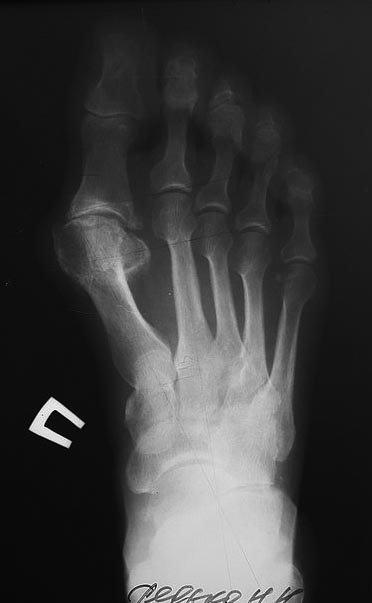

Пациентка 59 лет с деформацией стопы. Омозолелости под головками 2,3,4,5

плюсневых.

Плоскостопие и вальгусная деформация 1 пальца. Омозолелость над 2-м

межфаланговым суставом (видно на фото). План такой: SCARF 1 плюсневая с

укорочением, AKIN. вейль хохман 2 палец. открыто без внутренней

фиксации. Смущает то что по рентгенографии не преобладания длины 1 луча

они равны со 2-м, и омозолелости под 2,3,4. учитывая что 2 палец

деформирован клинически, планируется вмешиваться на нем. Но тогда и 3

делать открыто вейль и закрыто 4 вейль. Стоит ли трогать 3,4. и какие

замечания по плану? спасибо большое!